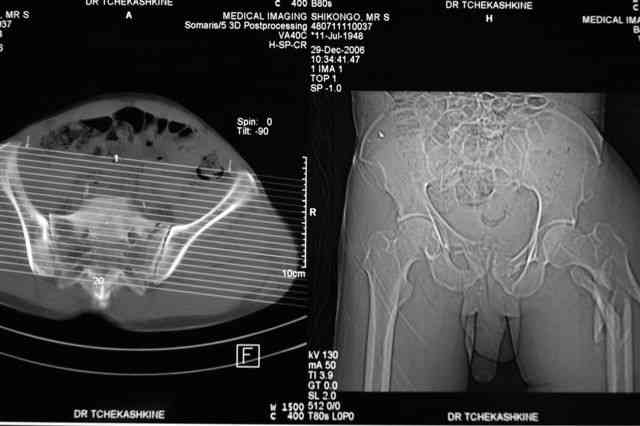

Уважаемые коллеги, Мужчина 58 лет в результате ДТП получил переломы 5-6-7 ребер справа (п\к эмфизема), вертикально-ротационно нестабильное повреждение тазового кольца, подвертельный перелом левого бедра, перелом внутр. лодыжки справа, пяточной кости справа.

Гемодинамика стабильна, НВ 10,2 г/л, Общ ан.крови, мочи - без патологии, Повреждения внутр. органов нет.

По техническим причинам стабилизация переломов в день травмы не была выполнена. До сегодняшнего дня находился на вытяжении.

Какова оптимальная последовательность фиксации на ваш взгляд:

таз-бедро- лодыжка в одну сессию

бедро- лодыжка сначала, фиксация таза через несколько дней,

фиксация бедра: реконструктивный гвоздь Смит/Нефью

PFN

Gamma nail long

DCS

95 Blade plate

метод фиксации таза: стержневой аппарат (тазового набора Илизарова нет в округе)

каннюлированными винтами,

передняя фиксация пластиной правого крестцово- подвздошного сочленения

После задней стабилизации есть ли необходимость фиксации переднего отдела : аппарат/ кан. винты?